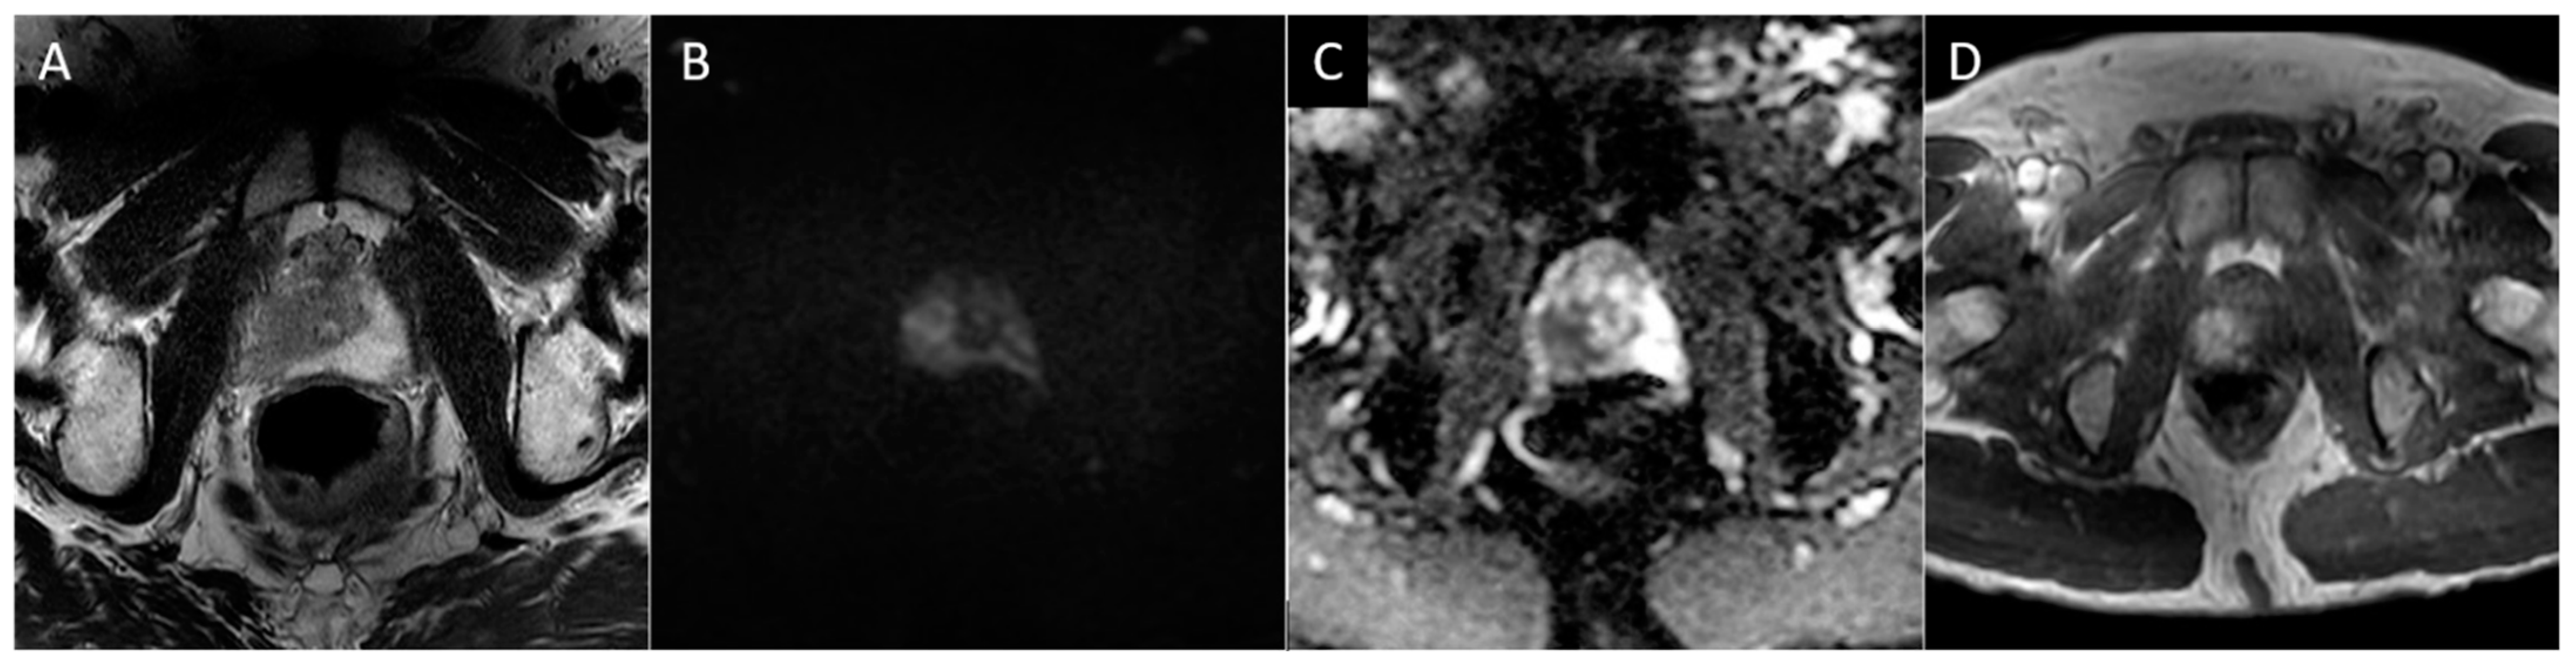

Figure 3. Whole-body maximum intensity projection (A), axial fused fluiclovine-PET/MRI (B), axial T2 (C), diffusion-weighted b2000 (D), apparent diffusion coefficient (E), and dynamic contrast-enhanced (F) images demonstrating focal uptake of radiotracer in the right prostatic apex peripheral zone with corresponding MR defined T2 hypointense lesion with associated restricted diffusion and focal asymmetric enhancement (PI-RADS 5), consistent with prostate cancer.

18F-fluciclovine functions as an analog of l-leucine amino acid, which is a transport protein preferentially upregulated in prostate cancer. Unlike many radiotracers used for prostate imaging, fluciclovine has minimal renal excretion, reducing confounding activity in the pelvis from urinary tract activity [59,60]. For initial staging, fluciclovine has limited value in localizing the primary prostate tumor, predominantly due to decreased specificity owing to overexpression in benign etiologies such as BPH and prostatitis [61]. However, fluciclovine performs better in the setting of biochemical recurrence, where updated NCCN guidelines recommend the consideration of fluciclovine PET imaging [62]. In the detection of extraprostatic disease, the tracer performs excellently, with a specificity of up to 100% for disease outside the prostate [63,64]. While the same studies demonstrated diminished specificity for detecting recurrent disease within the prostate itself, this highlights the role of concomitant mpMRI, as previously discussed (Figure 3).